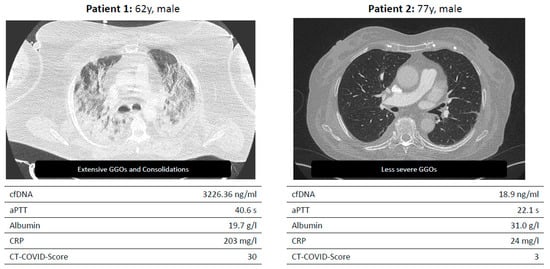

For the assessment of the diversity of the disease in COVID-19 severity and treatment, a comparison between the ICU- and non-ICU cohorts was performed. Moreover, this comparison revealed significantly elevated laboratory parameters in cases requiring ICU admission (Table 1/Figure 2). Participants in whom CT could be assessed for pulmonary embolism were not observed to have a central or distal embolism.

Exemplary presentation of two test persons with severe and mild progression.

Figure 2. Two example patients enrolled in the LAGGO study.